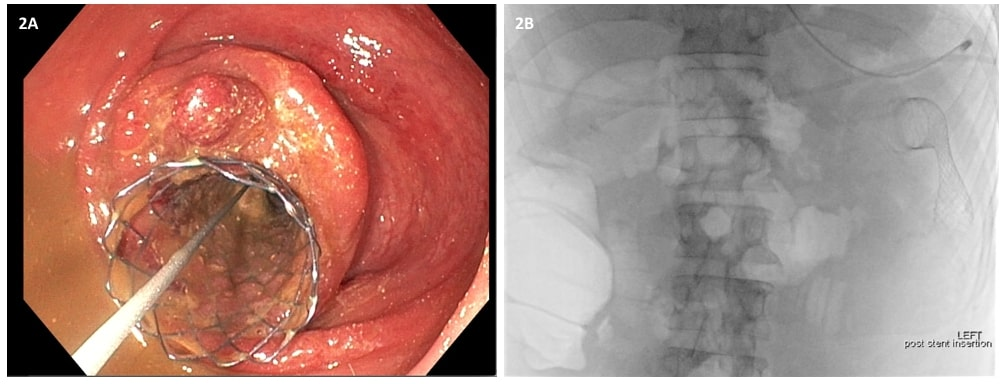

在术后第1天和第2天,重复进行X线检查以评估支架置入情况(图3)。

腹部和盆腔CT显示脾曲周围有一段环周狭窄伴壁增厚、肠袢近端扩张和慢性胰腺炎特征(图1A-C)。鉴于CEA升高和贫血,初步判断是由脾曲恶性肿瘤引起的肠梗阻。因此对患者行内镜下支架置入术(图2A-B)。但发生了早期支架移位(图3A-C),这种情况非常罕见。因此,患者在内镜下支架置入术后6天行早期腹腔镜下左半结肠切除术,以切除梗阻病变,防止支架移位造成再梗阻。